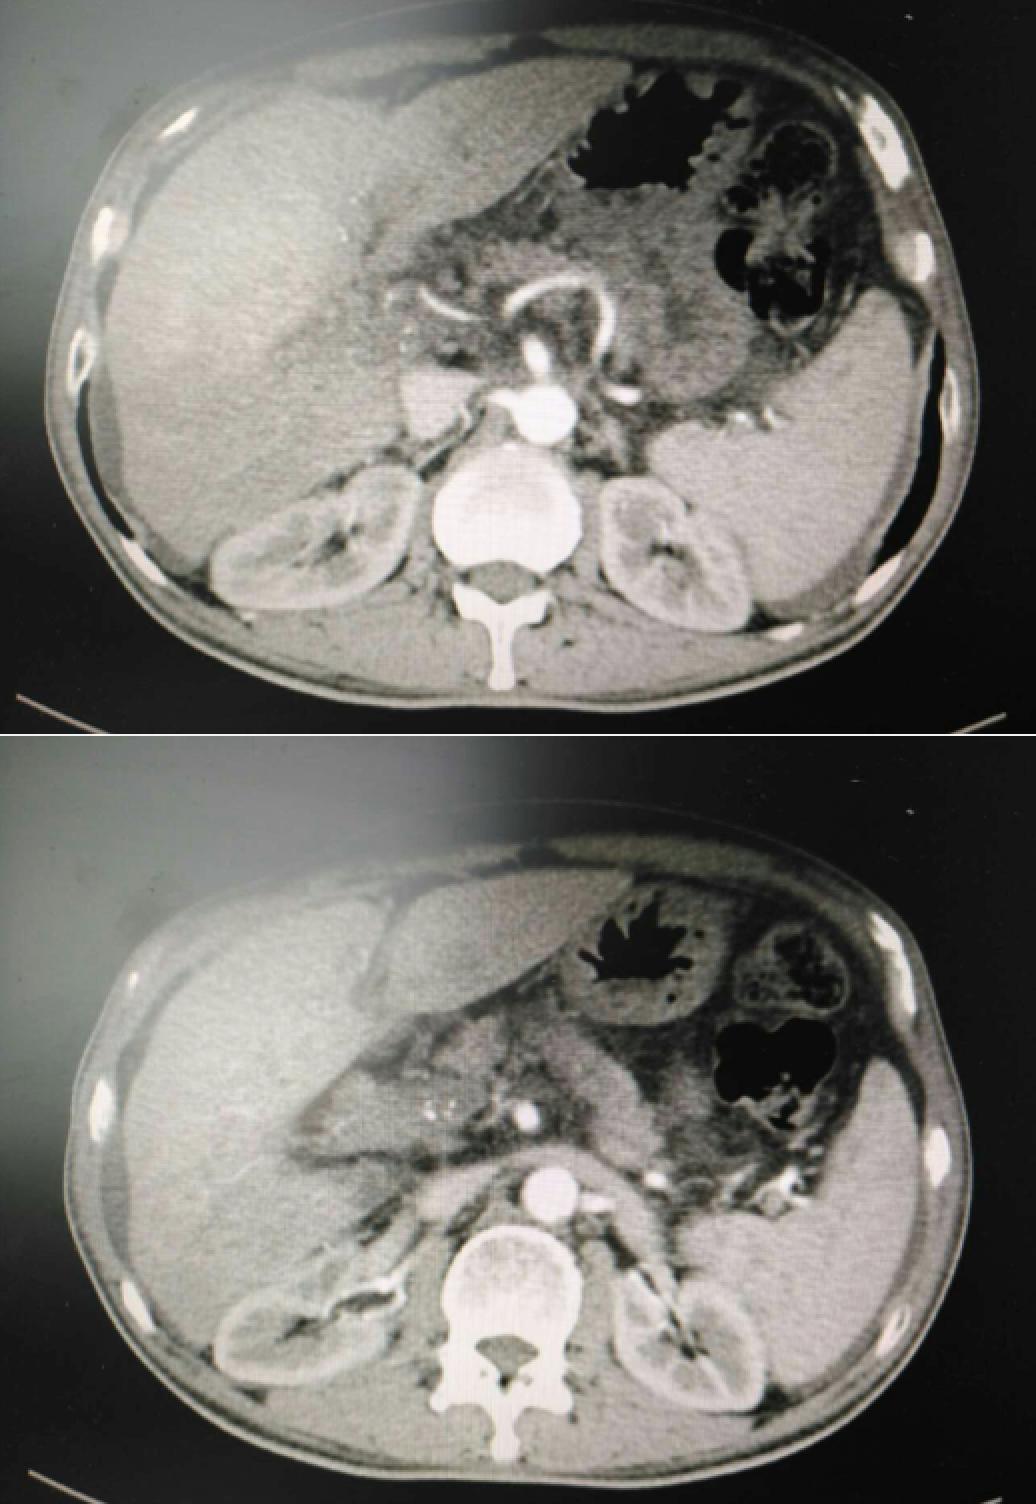

患者因纳差、烧心、腹痛、腹胀2月,于2016-01-17在某县人民医院行腹部CT示肝癌并门脉癌栓形成。分别于2016-01-22、2016-02-19于某市医院行两次TACE术(具体不详)。患者介入术后规律服用抗乙肝病毒、保肝、提高免疫力等药物治疗。2016-02-03至2016-04-30在某省立医院行5周期CIK免疫治疗。2016-05-18至2016-05-25于我院行射波刀治疗门静脉癌栓,具体放疗计划为:42Gy/7F。2016-06-24在我院行肝右动脉化疗栓塞术+肝右动脉灌注化疗术+间接门脉灌注化疗术,术中化疗总量,吡柔比星2mg、顺铂12mg、氟尿嘧啶250mg。分别于2016-05-10、2016-05-27、2016-06-13、2016-07-01、2016-07-27、2016-08-22、2016-09-19、2016-10-07、2016-10-19、2016-11-18、2016-12-18、2017-02-18行12周期免疫治疗。自2016-05-12起患者间断口服靶向药物阿帕替尼250-500mg/d,血压维持在220-130/95-70mmHg,血压升高期间伴上腹部不适,左侧为著,并向腰背部放射,偶尔反酸、烧心,剑突下疼痛,口服抑酸剂或进食后缓解,临床诊断为十二指肠溃疡,目前口服奥美拉唑、马来酸依那普利、氢氯噻嗪等药物对症降压。2017-03-02于我院行第二次肝右动脉化疗栓塞术+肝右动脉灌注化疗术+间接门脉造影术+肠系膜上动脉灌注化疗术。术中化疗总量,洛铂10mg、氟尿嘧啶500mg、吉西他滨400mg。目前间或皮下注射胸腺法新、重组人干扰素α-2b提高免疫力及慢性乙型病毒性肝炎治疗效果。

患者相关影像资料